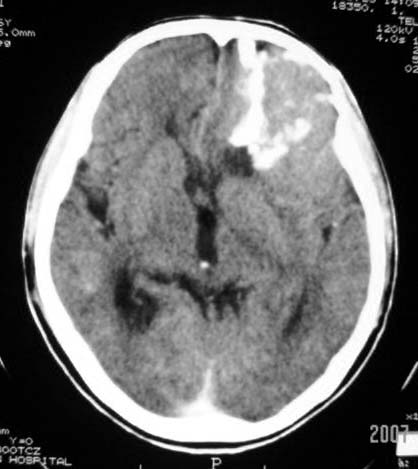

标题: CT7268:左额顶部病变增强片. [打印本页]

标题: CT7268:左额顶部病变增强片.

左额叶病灶内条片状高密度是钙化吗?是的话考虑少支胶质瘤可能大。不然有脑血畸形伴出血可能。

左侧额顶叶有条带状钙化的不规则形占位,增强呈不均匀轻度强化,局部颅骨受侵蚀变薄,典型的少支胶质细胞瘤。

比较典型的少枝胶质细胞瘤ct表现,局部额骨垂直板有侵蚀变薄